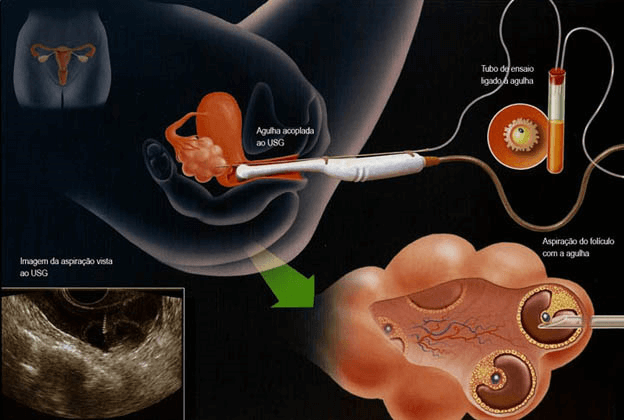

Os ovários normalmente estimulam e liberam um óvulo por mês. No tratamento precisamos otimizar essa produção, pois assim aumentaremos o número de embriões a serem congelados. Para isso a mulher deverá usar hormônios por aproximadamente 10 dias, período onde o médico fará alguns exames de ultrassonografia para acompanhar o desenvolvimento dos óvulos.

Após a estimulação os óvulos são coletados num procedimento bastante tranquilo que demora aproximadamente 15-20 min. e é realizado com um ultrassom transvaginal, chamado de aspiração ovariana. Não tem corte e não costuma causar nada além de leve desconforto abdominal por algumas horas depois de feito.

Os óvulos coletados são então injetados com o espermatozoide do parceiro, para iniciar o desenvolvimento dos embriões, que devem ser congelados com 3 ou 5 dias de evolução.